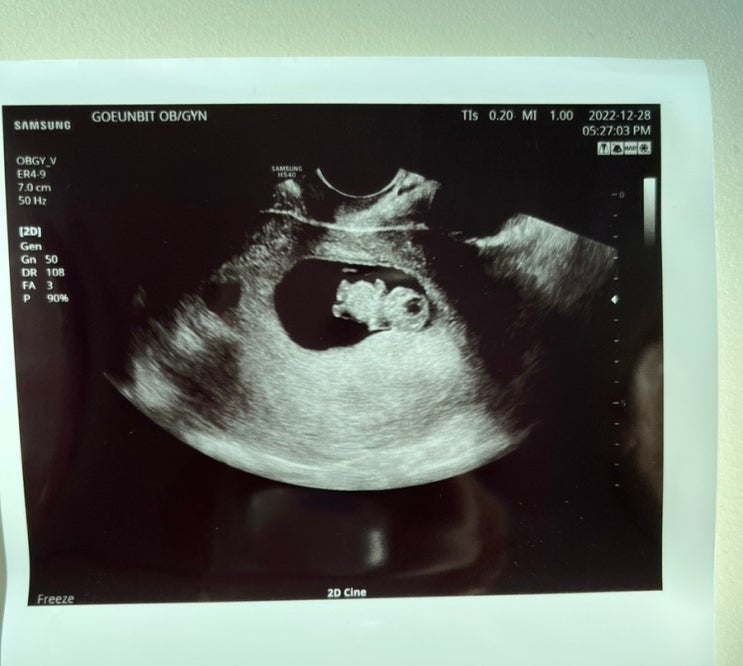

임신 9-11주차 증상: 입덧 절정/젤리곰 확인/입덧음식 추천

임신 9주차 증상 기록 연말연시를 입덧 절정으로 힘겹게 보냈던 임신 9주차 일상 기록 9주차에 어플 기록한...